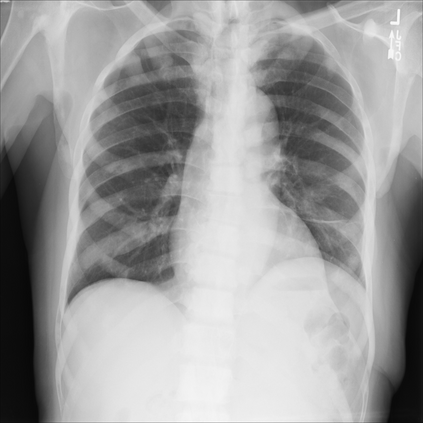

The integration of deep learning systems into healthcare has been hindered by the resource-intensive process of data annotation and the inability of these systems to generalize to different data distributions. Foundation models, which are models pre-trained on large datasets, have emerged as a solution to reduce reliance on annotated data and enhance model generalizability and robustness. DINOv2 is an open-source foundation model pre-trained with self-supervised learning on 142 million curated natural images that exhibits promising capabilities across various vision tasks. Nevertheless, a critical question remains unanswered regarding DINOv2's adaptability to radiological imaging, and whether its features are sufficiently general to benefit radiology image analysis. Therefore, this study comprehensively evaluates DINOv2 for radiology, conducting over 100 experiments across diverse modalities (X-ray, CT, and MRI). To measure the effectiveness and generalizability of DINOv2's feature representations, we analyze the model across medical image analysis tasks including disease classification and organ segmentation on both 2D and 3D images, and under different settings like kNN, few-shot learning, linear-probing, end-to-end fine-tuning, and parameter-efficient fine-tuning. Comparative analyses with established supervised, self-supervised, and weakly-supervised models reveal DINOv2's superior performance and cross-task generalizability. The findings contribute insights to potential avenues for optimizing pre-training strategies for medical imaging and enhancing the broader understanding of DINOv2's role in bridging the gap between natural and radiological image analysis. Our code is available at https://github.com/MohammedSB/DINOv2ForRadiology